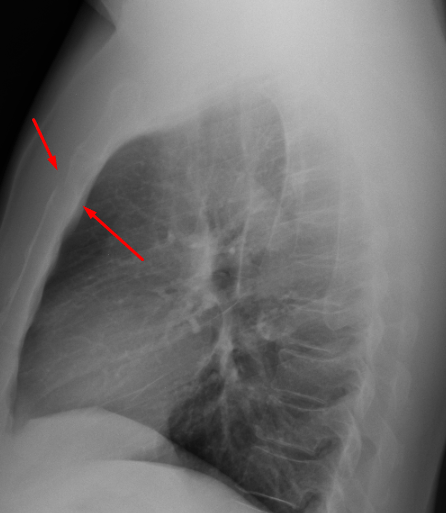

Age: 55

Sex: Male

Indication: Persistent chest pain

Sample ReportAcute mildly displaced sternal body fracture. Recommend chest CTA to further assess for mediastinal injury.

Otherwise, no evidence of acute cardiopulmonary disease.